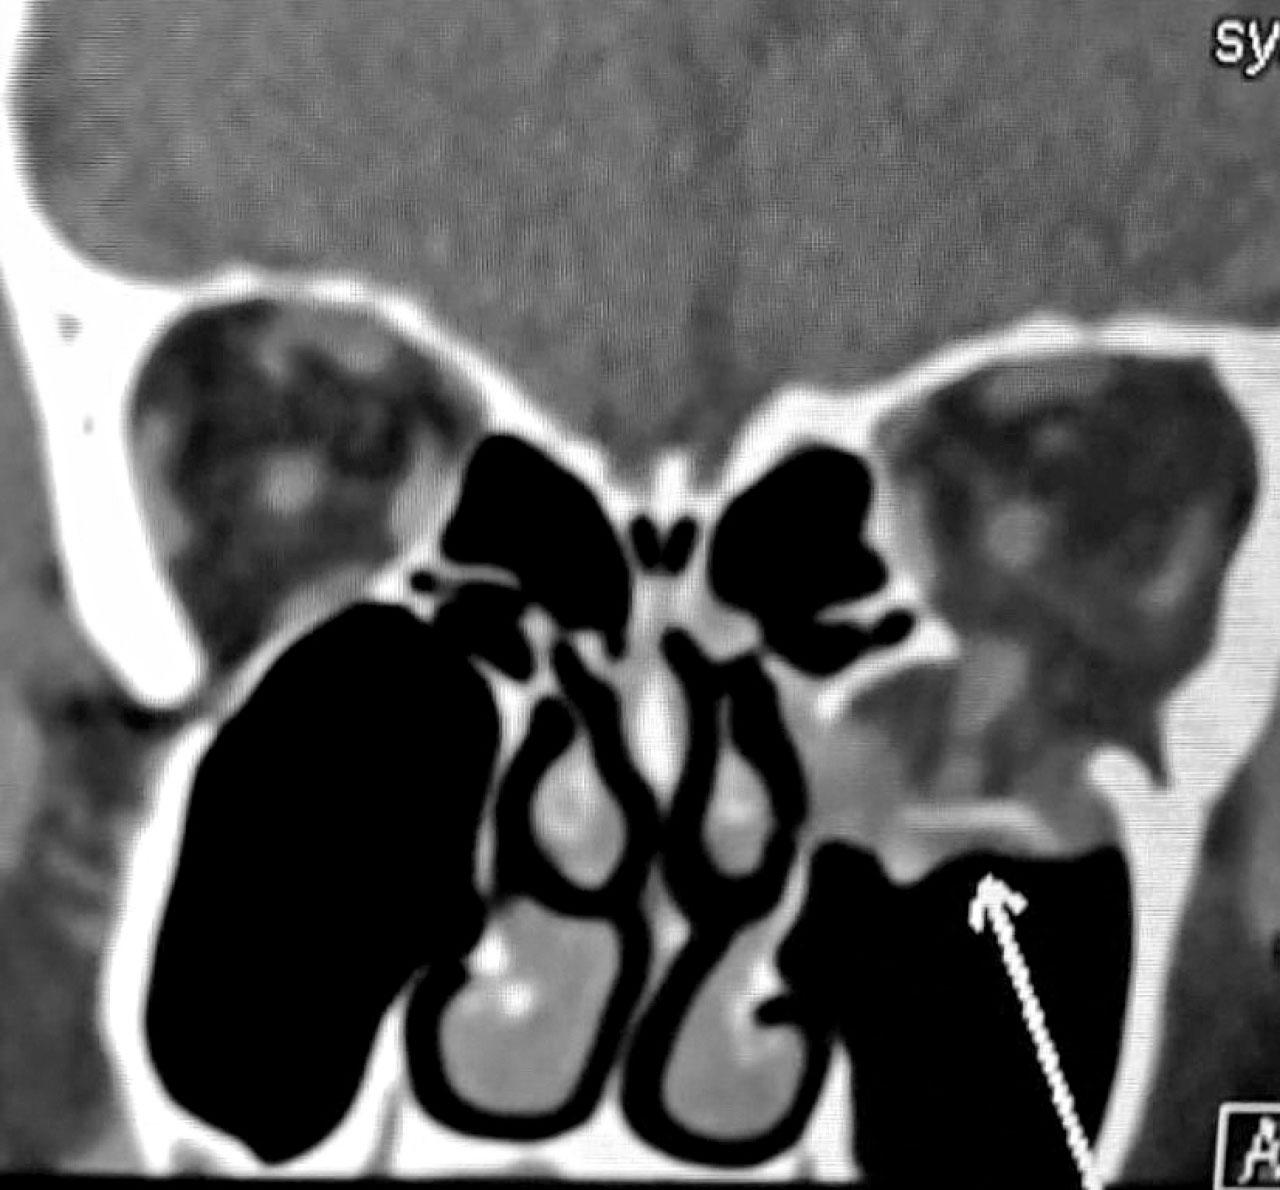

當眼球受到外力的撞擊時,除了眼窩骨折,也有可能同時導致眼球本體受傷,如結膜出血、前房積血、創傷性白內障、晶體移位、玻璃體出血、視網膜撕裂或視網膜脫落、視神經傷害等有可能嚴重影響視力的情況,因此必須由眼科專科醫生全面檢查及診斷,再配合電腦斷層掃描(CT scan),詳細評估眼窩壁是否有骨折、其嚴重程度,及可能伴隨的相關顏面骨折,最常見的為顴骨骨折。因應骨折的範圍和影響,制訂治療方案。下期續談眼窩骨折的治療和手術。